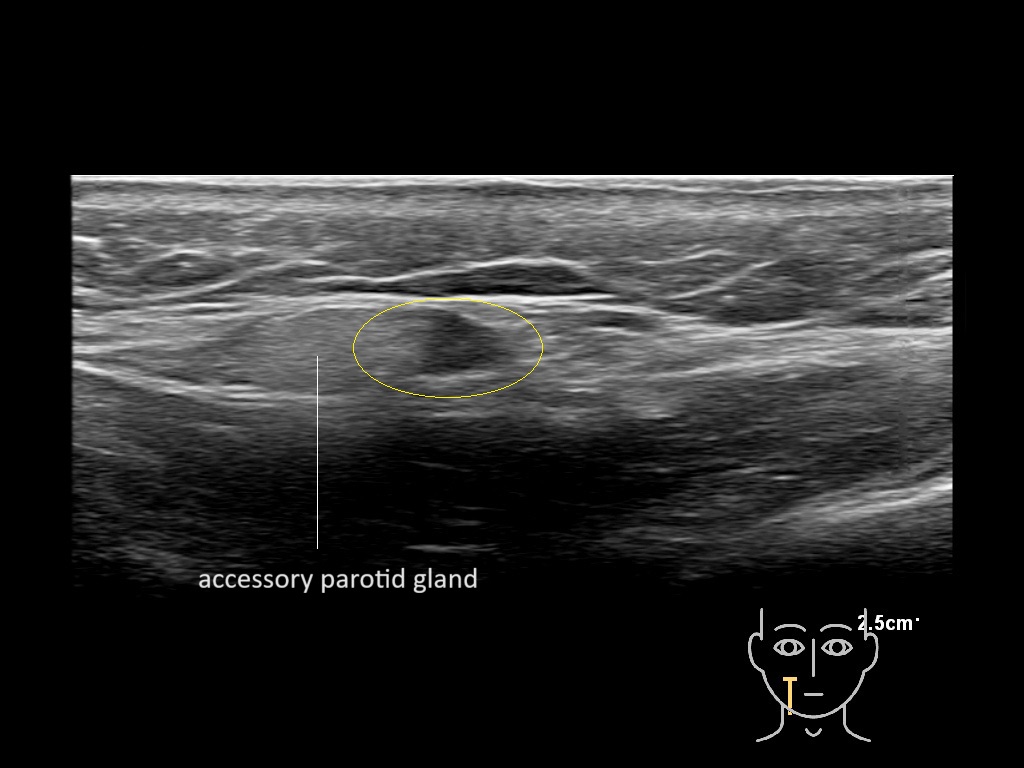

Filler injections in the parotid gland may go unnoticed, however, inflammatory reactions and abscesses may occur. Hypervascularity can be seen with color doppler. Filler deposits are supposed to be injected into the superficial fatty layer . The space to inject into this layer may be limited. Routinely we measure a width of 2-4 millimeters with sometimes subcutaneous layers being less than one millimeter thick.

Study the first image to recognize the different layers. If you are sure about the layers, swipe to the second image to view the answer (if applicable).